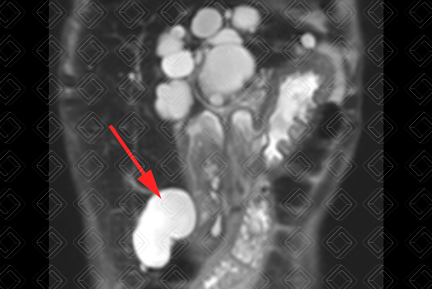

Texto alternativo para a imagem Figura 2. Créditos: Dra. Elazir Mota - Rio de Janeiro/RJ

Descrição das figuras 1 e 2: Ressonância magnética. Imagens ponderadas em T2 (sequência HASTE), plano coronal e axial, evidenciando imagens com contornos lobulados e alto sinal em T2, algumas com septos internos, dispersos pelo parênquima hepático (setas vermelhas).

• Ressonância magnética do abdome com contraste venoso: O cisto simples em geral é redondo, com sinal homogêneo, baixo em T1 e alto em T2. O contorno é regular e a parede imperceptível. Não há realce no estudo pós-contraste.